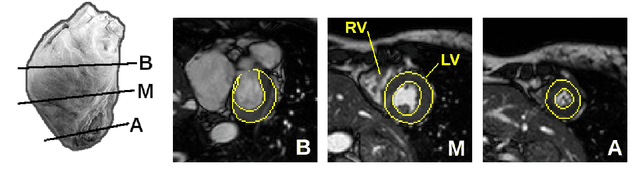

Abstract:Magnetic resonance imaging (MRI) is a widely known medical imaging technique used to assess the heart function. Deep learning (DL) models perform several tasks in cardiac MRI (CMR) images with good efficacy, such as segmentation, estimation, and detection of diseases. Many DL models based on convolutional neural networks (CNN) were improved by detecting regions-of-interest (ROI) either automatically or by hand. In this paper we describe Visual-Motion-Focus (VMF), a module that detects the heart motion in the 4D MRI sequence, and highlights ROIs by focusing a Radial Basis Function (RBF) on the estimated motion field. We experimented and evaluated VMF on three CMR datasets, observing that the proposed ROIs cover 99.7% of data labels (Recall score), improved the CNN segmentation (mean Dice score) by 1.7 (p < .001) after the ROI extraction, and improved the overall training speed by 2.5 times (+150%).